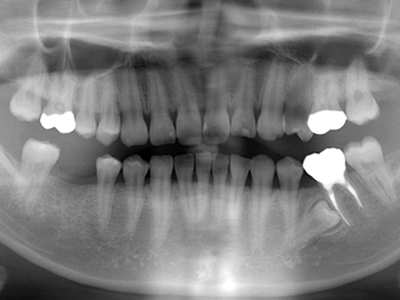

1. 初診時X線パノラマ

平成19年の年末に初めて来院した時のX線パノラマです。主訴が右下6番の銀歯の脱離との事ですが、同部はもう残根となり抜歯必至です。他には上顎親知らず。左上4番の転位歯、左下5番の埋伏と6番の不良根充が目立ちます。

2. 初診時右下6番X線デンタル

初診時の主訴であった右下6番の歯冠が脱離した部位のX線デンタルです。患者様は銀歯が脱離してしばらく放置したとのことで、痛みもないので又歯冠をつければ良い位に考えていた様子でした。歯根吸収の状況より当時22歳とのことで、相当若年時に抜髄されたのが想像できます。考えてみれば6歳に萌出して15年で抜歯となった訳です。上顎8番の同部への移植も考慮しましたが断念しました。

3. 左下根治前X線

やはり初診時の左側6番部です。5番が埋伏してその歯冠が6番の近心に被っています。乳歯列交換期おそらく7〜10歳位に6番を露髄させ、生切して乳歯Eを早期抜歯し、その後の保隙処置がなされなかったと思われます。

4. 左下6番根治後X線

左下5,6番部に関しては悩みました。6番が失活で不良根充です。6番のみならず埋伏している5番までダメになると思われます。埋伏歯を抜歯して6番を再根治するか?根治してもやはり失活は弱いので、6番を抜歯して5番をエクストルージョン(矯正にて引っ張り出す)するか?患者様には説明を何度も繰り返し、ご自身で選択してもらいました。歯科医任せではダメという認識が芽生えたようです。結局6番は再根治して出来るだけ保存し、ダメになるようなら抜歯して5番を引っ張り出す展望で経過観察とします。